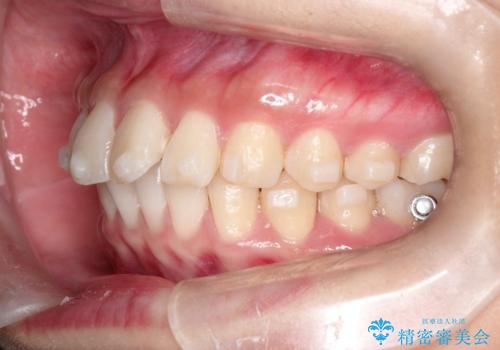

【インビザライン】翼状捻転+出っ歯を治したい

- 前歯の捻れと口元の突出を主訴に来院されました。

インビザラインを用いて上顎の遠心移動を行い、前歯を下げながら凸凹を綺麗に治すことができました。

歯を抜かない矯正治療を行う場合、口元は極端には変わりません。

今回は奥歯の遠心移動を行い、できる限り前歯を下げられるように治療を行いました。